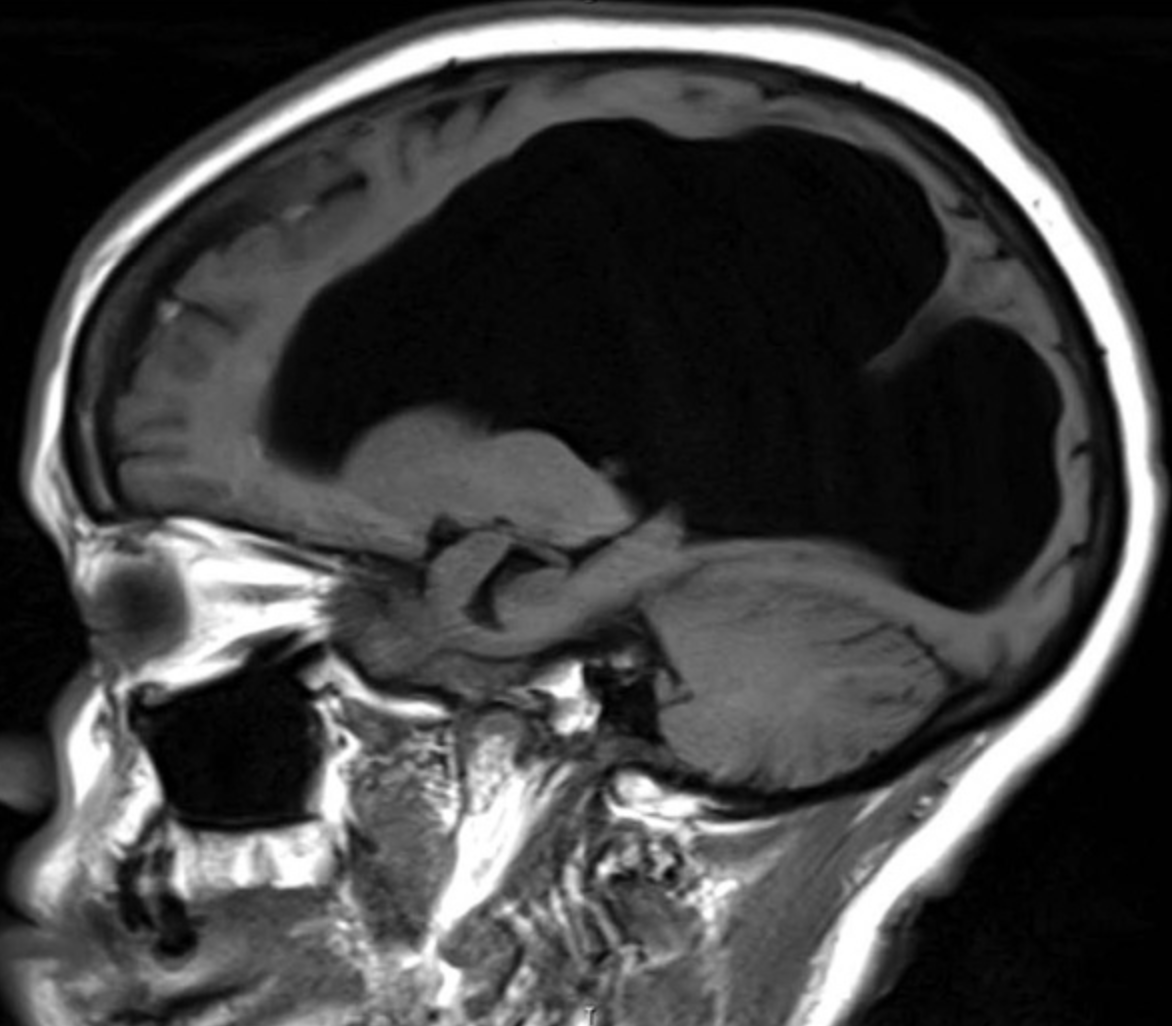

Mujer de 62 años que ingresó grave al hospital por sepsis secundaria a neumonía. Se tomaron estudios de neuroimagen mostradas aquí. Se encontró en ellas una hidrocefalia compensada probablemente desde el nacimiento. https://www.thelancet.com/journals/lancet/article/PIIS0140-6736(16)00089-1/fulltext …

#caso#medicina pic.twitter.com/pct3PsIWBu